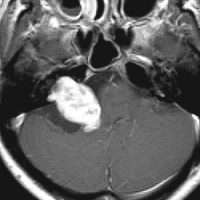

聴神経腫瘍でまず手術が必要なのは巨大なものです。この4枚の写真は私が実際に手術をした患者さんのものです。脳幹部という脳の最も大切なところが腫瘍によって圧迫されて変形しているのが特徴です。右上のものはのう胞性腫瘍なので大きさの割に手術のリスクは高くありませんが,左上のものは実質性で出血性のものですごくリスクが高い手術でした。左下のものは普通のリスク。右下のものは超高難易度のものです。